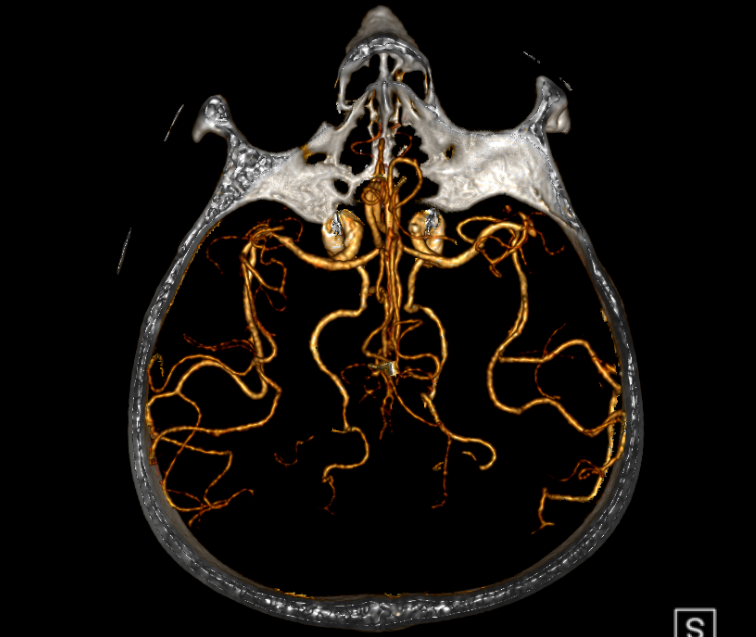

CTA提示右侧大脑中动脉M2段下干闭塞。

动脉长鞘怎么置入有励可说|Locaste 088励楷长鞘及Tarvos微导丝在右侧大脑中动脉M2段取栓术中的应用_https://www.jmylbn.com_新闻资讯_第6张

CTP提示核心梗死体积2.4ml,Mismatch体积160.8ml,低灌注区体积163.2ml,Mismatch比值为68。